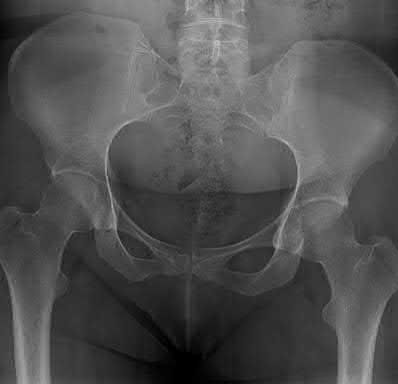

A poly-trauma patient presents hemodynamically unstable with an anteroposterior compression (APC-III) pelvic ring injury. A circumferential pelvic binder is requested to reduce pelvic volume and control hemorrhage. To be anatomically effective, the binder must be centered precisely over which of the following landmarks?

Correct Answer: Greater trochanters

For optimal mechanical advantage and effective reduction of an 'open book' pelvic fracture (APC type), a pelvic binder must be applied directly over the greater trochanters of the femurs. Applying it higher, such as over the iliac crests, is a common error that fails to adequately close the pelvic ring and can paradoxically open the true pelvis.